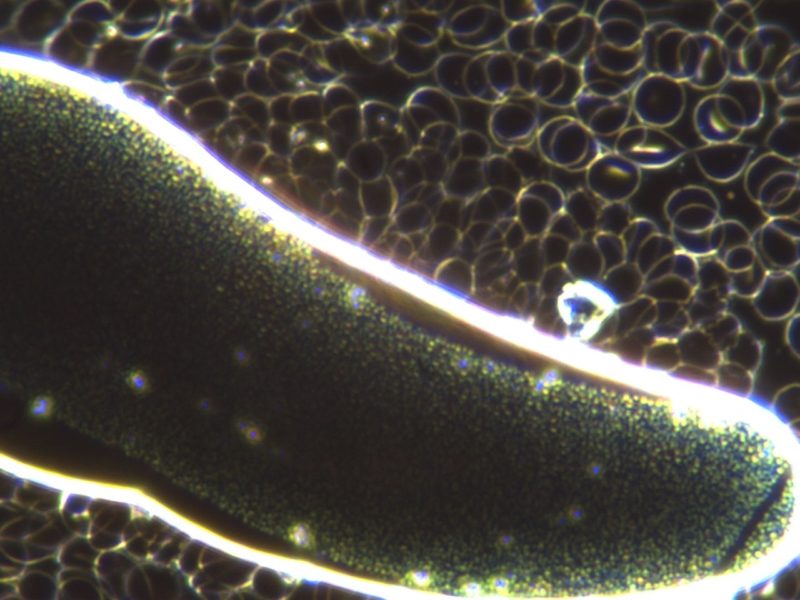

Ida zeigt eine hochgradige chronische Ohrentzündung (Otitis externa) und Hautausschlag. Zur Abklärung der Ursache haben wir allgemeine Blutuntersuchungen, Dunkelfeldanalysen, Hautgeschabsel, Tupferproben der Ohren, sowie einen Blut-Allergietest durchgeführt. In der allgemeinen Blutuntersuchung zeigt Ida dickes Blut und hohe Globulinwerte (Hinweis auf eine Allergie). In der Dunkelfeldanalyse (Fluoreszierendes Mikroskop durch das man einen Einblick in das lebendige Blut erhält) zeigt die Hündin eine starke Übersäuerung (Säureblasen), dickes Blut (Histaminose) und ein überlastetes Immunsystem (zugrunde gegangene weiße Blutkörperchen = Symblasten).

Histamine sind Gewebs- und Abwehr-Hormone, welche bei zu stark sensibilisierten Organismen zu viel gebildet werden und zu wenig von einem inaktiven Darmsystem und den Nieren ausgeschieden werden. Dies hat einige Auswirkungen: Das Blut wird schwerfähig, die kapilläre Durchblutung und damit die Sauerstoff- und Nährstoffversorgung wird beeinträchtigt. Im Hautgeschabsel sehen wir Malassezia Pilze (Hefepilze – meist sekundär zu einer Allergie). Die Tupferproben der Ohren ergeben die Besiedelung mit vorwiegend resistenten Keimen (Pseudomonaden und Enterokokken). Der Allergietest ergibt eine Allergie auf Rind und Soja, sowie auf Milben, Pollen und Flohspeichel. In der Ausdifferenzierung der Milben wird deutlich, dass Ida eine Hausstaubmilben- und Futtermilbenallergie zeigt. Zusammenfassend zeigt der Basset eine Ohrentzündung und eine Atopische Dermatitis (Hautentzündung) durch eine Malasseziainfektion.

Die Symptomatik von Idas Haut ist nach dieser Behandlung nahezu vollständig verschwunden. Einzig und allein das Ohr macht uns noch aufgrund der resistenten Keime und der starken Hängeohren der Bassets zu schaffen. Eine Besserung konnten wir bereits erzielen, eine Heilung ist noch zu erwarten. Unseren Therapieerfolg erkennen wir nicht nur in Idas verbesserter Symptomatik, sondern auch in der Kontrolle der Dunkelfeldanalyse.